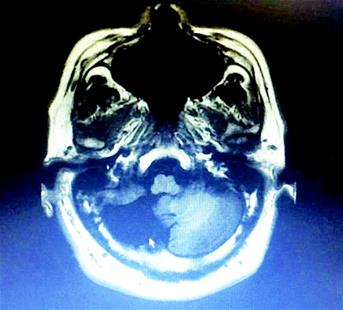

男子仅半个小脑却无异常人 打篮球一投一个准